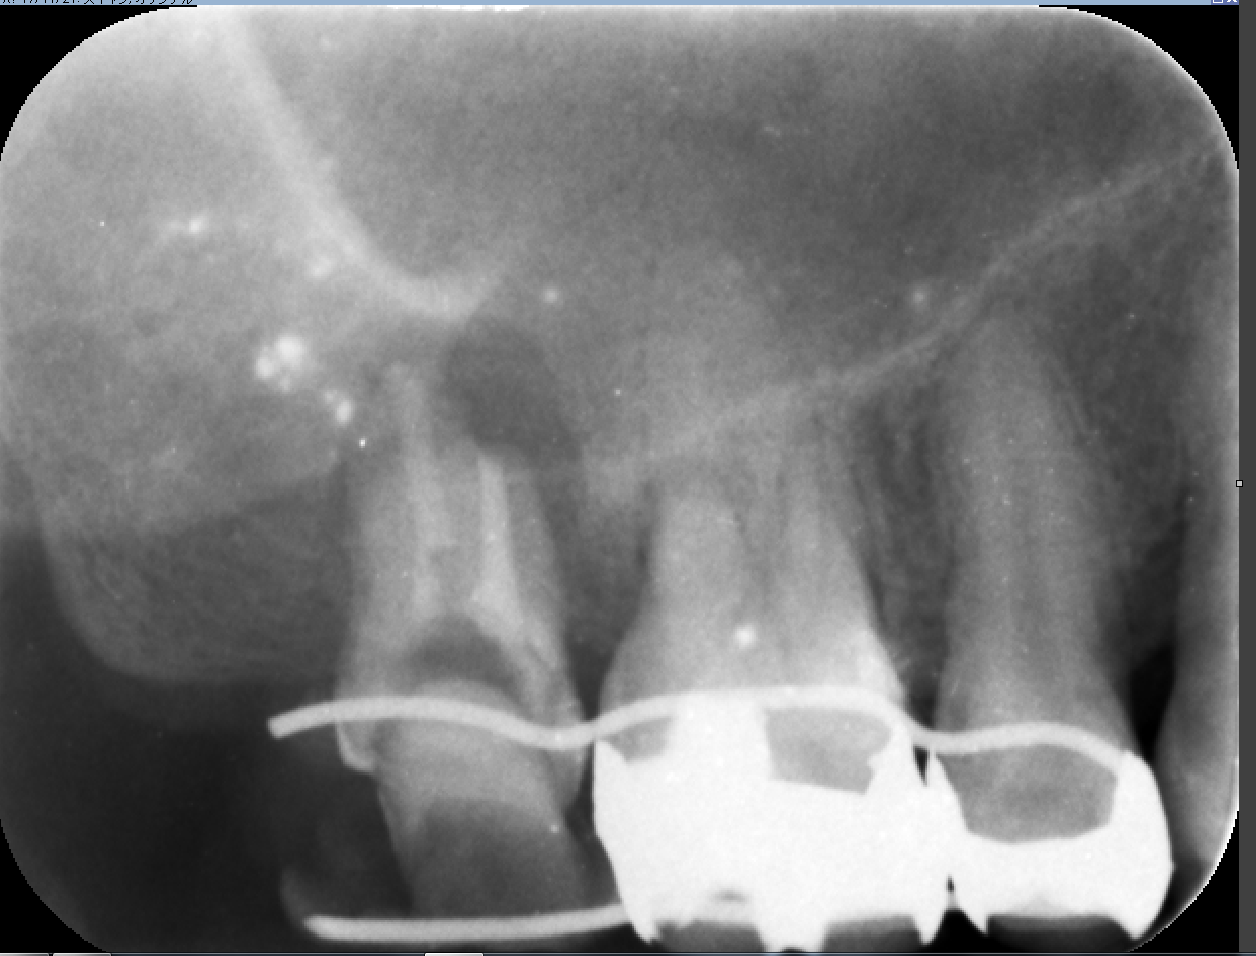

1ケース目マイクロエンド

このケースは根尖の感染が大きく通常の根管充填では精密につめれません。MTAセメントを手で練っていきます。

MTAはガッタパーチャより薄く写ります。指でも抜けるくらいの歯が回復してきています。